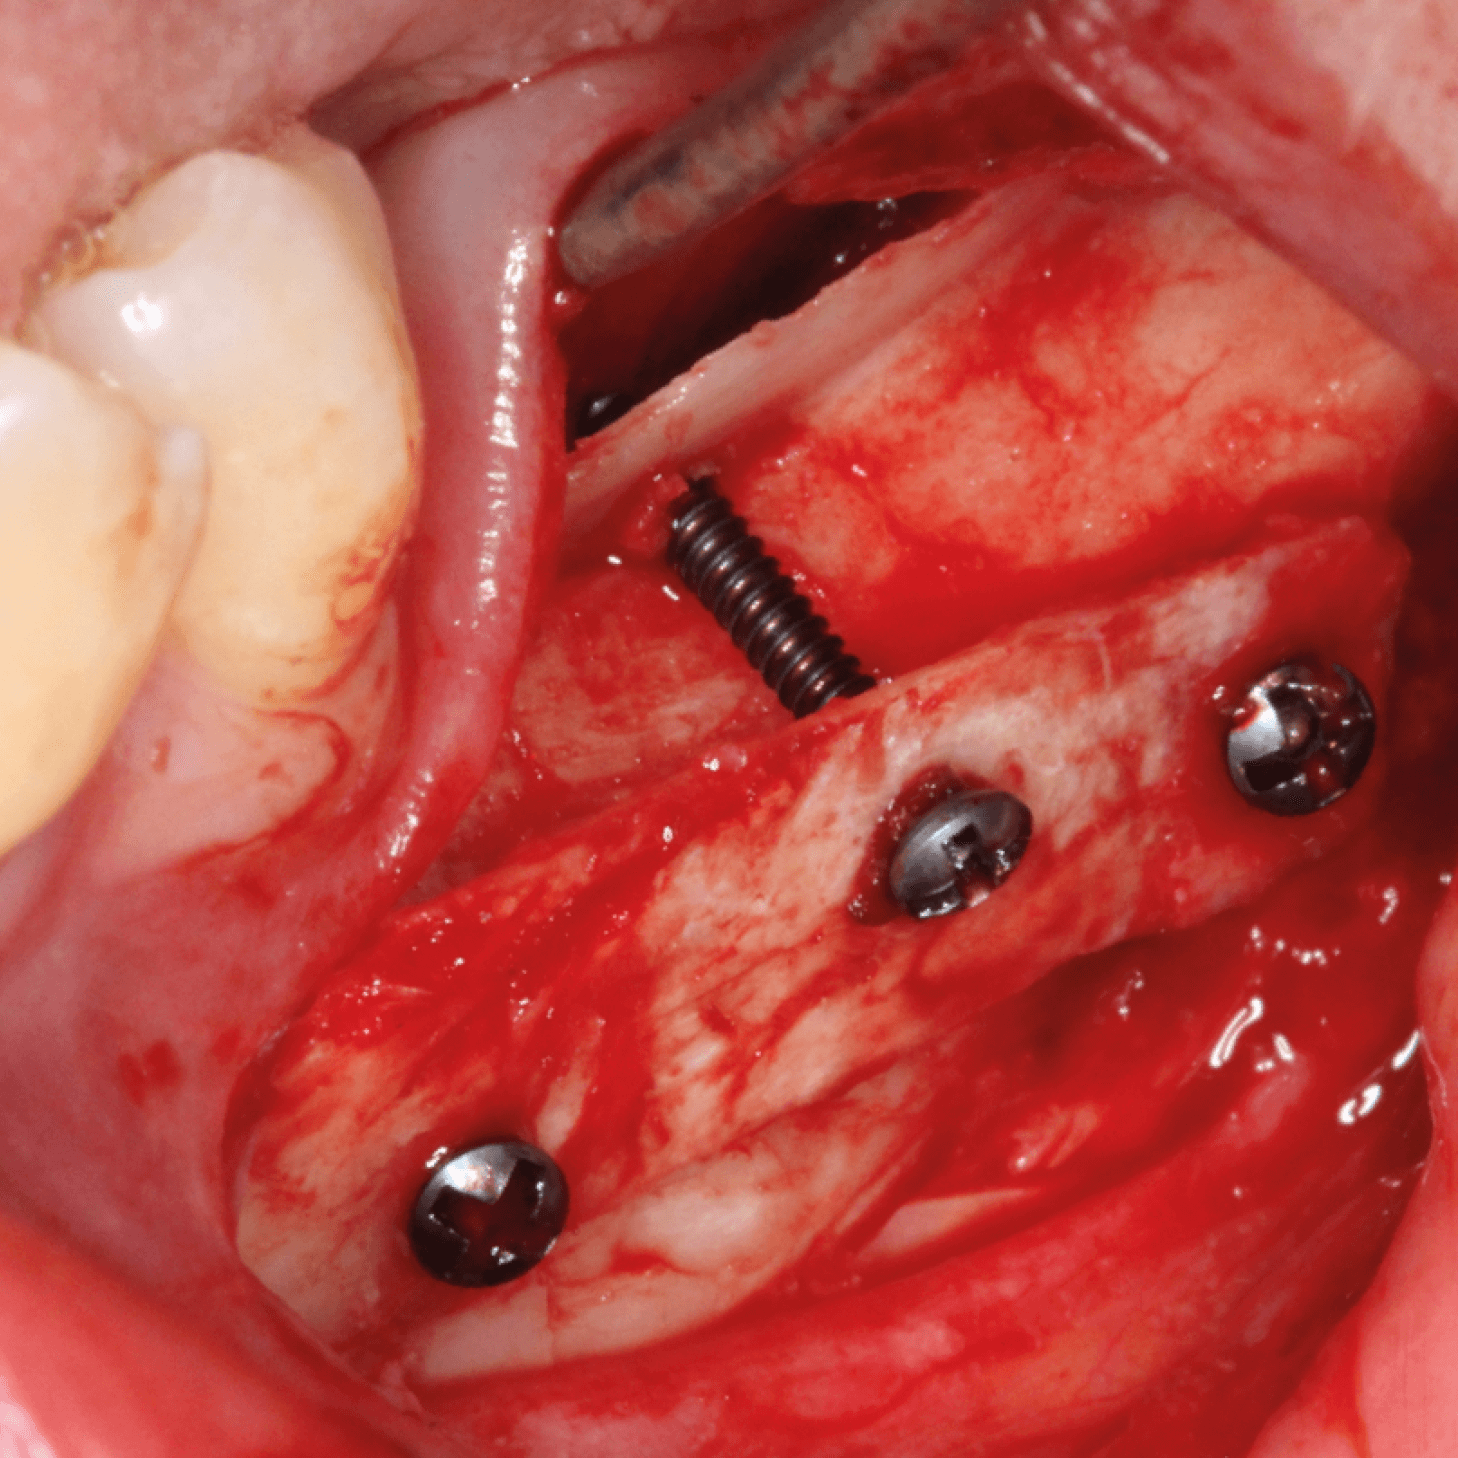

Im Gebiet der Hart- und Weichgewebechirurgie sowie der oralen Implantologie stellen erfahrene Referenten vor, welche Materialien sich für welchen Einsatz und welche Indikationen eignen. In Vortragsveranstaltungen, aber auch bei Live-OP-Kursen und Hands-on-Übungen lernen Sie den Einsatz der Biomaterialien besser kennen und können das Erlernte bei praktischen Übungen gleich direkt anwenden.